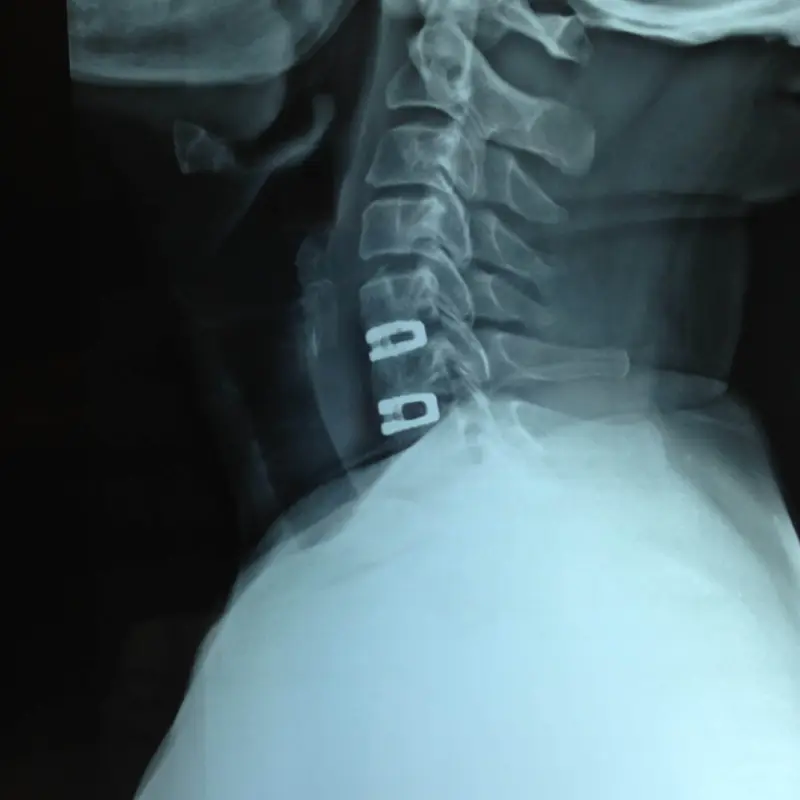

Cervical Disc Replacement